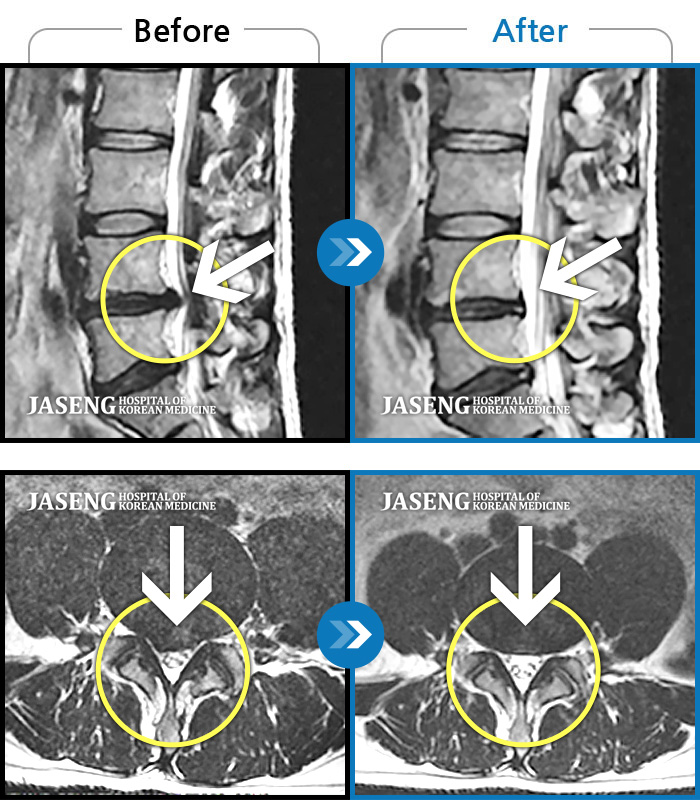

Xray 와 MRI 검사를 받았고

4번5번 척추사이 협착증과 유종이 원인이라고 하면서

한방 비수술치료로 2달동안 치료하면 나을 수가 있다고 말씀하셨고, 만약 한방치료로도 낫지 않으면 큰 대학병원 수술을 받아야 한다고 하면서 한방 비수술 치료를 권장해 주셔서, 박정우원장님의 치료를 받기 시작하였다.

12월20일까지 두 달 정도 치료를 마친 결과,

거의 정상상태로 회복 되었으며, 현재는 집에서 꾸준하게 체조와 가벼운 운동으로 관리하고 있습니다.